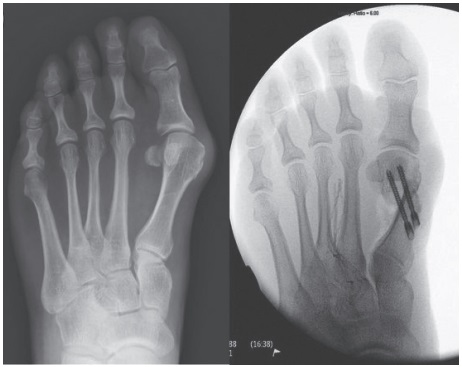

The term hallux valgus means a bunion. This occurs when the big toe joint is leaning into the second toe too much. As the bunion size increases it can start to rub against your shoes causing redness and pain. The foot shape also changes as weight is distributed through the foot differently, increasing foot pain. It is at this stage that surgical intervention is often considered.

The aim of this surgery is to correct alignment of the toes. During conventional surgery, a cut is made to the inside of your big toe, usually around 5cm in length.

With the minimally invasive technique used for hallux valgus surgery, four 3mm cuts are made around the big toe. The surgeon is then able to divide the soft tissue to locate the bone, and make the required osteotomy (cutting of a bone to reshape it through healing).